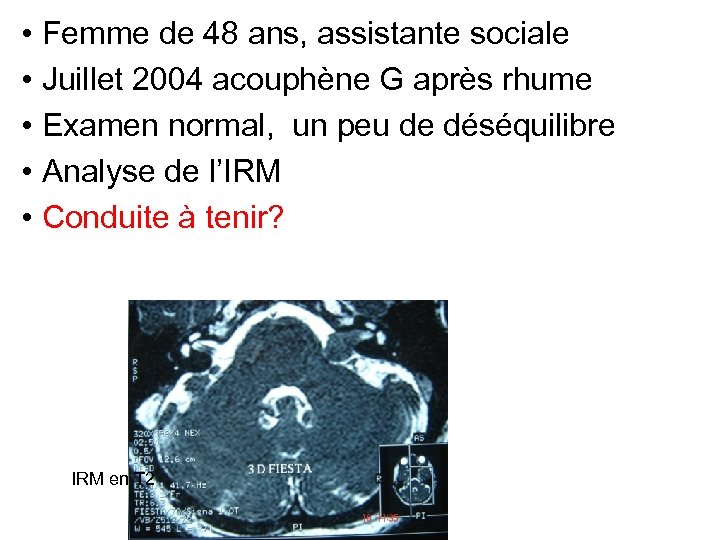

• Femme de 48 ans, assistante sociale • Juillet 2004 acouphène G après rhume • Examen normal, un peu de déséquilibre • Analyse de l’IRM? IRM en T 2

• Femme de 48 ans, assistante sociale • Juillet 2004 acouphène G après rhume • Examen normal, un peu de déséquilibre • Analyse de l’IRM? IRM en T 2

Analyse de l’IRM • Volume, taille, stade de tumeur • Vacuité du CAI • Place du canal semi circulaire postérieur

Analyse de l’IRM • Volume, taille, stade de tumeur • Vacuité du CAI • Place du canal semi circulaire postérieur

• Femme de 48 ans, assistante sociale • Juillet 2004 acouphène G après rhume • Examen normal, un peu de déséquilibre • Analyse de l’IRM • Conduite à tenir? IRM en T 2

• Femme de 48 ans, assistante sociale • Juillet 2004 acouphène G après rhume • Examen normal, un peu de déséquilibre • Analyse de l’IRM • Conduite à tenir? IRM en T 2